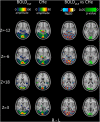

The physiological pulsations that drive tissue fluid homeostasis are not well characterized during brain activation. Therefore, we used fast magnetic resonance encephalography (MREG) fMRI to measure full band (0-5 Hz) blood oxygen level-dependent (BOLDFB) signals during a dynamic visual task in 23 subjects. This revealed brain activity in the very low frequency (BOLDVLF) as well as in cardiac and respiratory bands. The cardiovascular hemodynamic envelope (CHe) signal correlated significantly with the visual BOLDVLF response, considered as an independent signal source in the V1-V2 visual cortices. The CHe preceded the canonical BOLDVLF response by an average of 1.3 (± 2.2) s. Physiologically, the observed CHe signal could mark increased regional cardiovascular pulsatility following vasodilation.